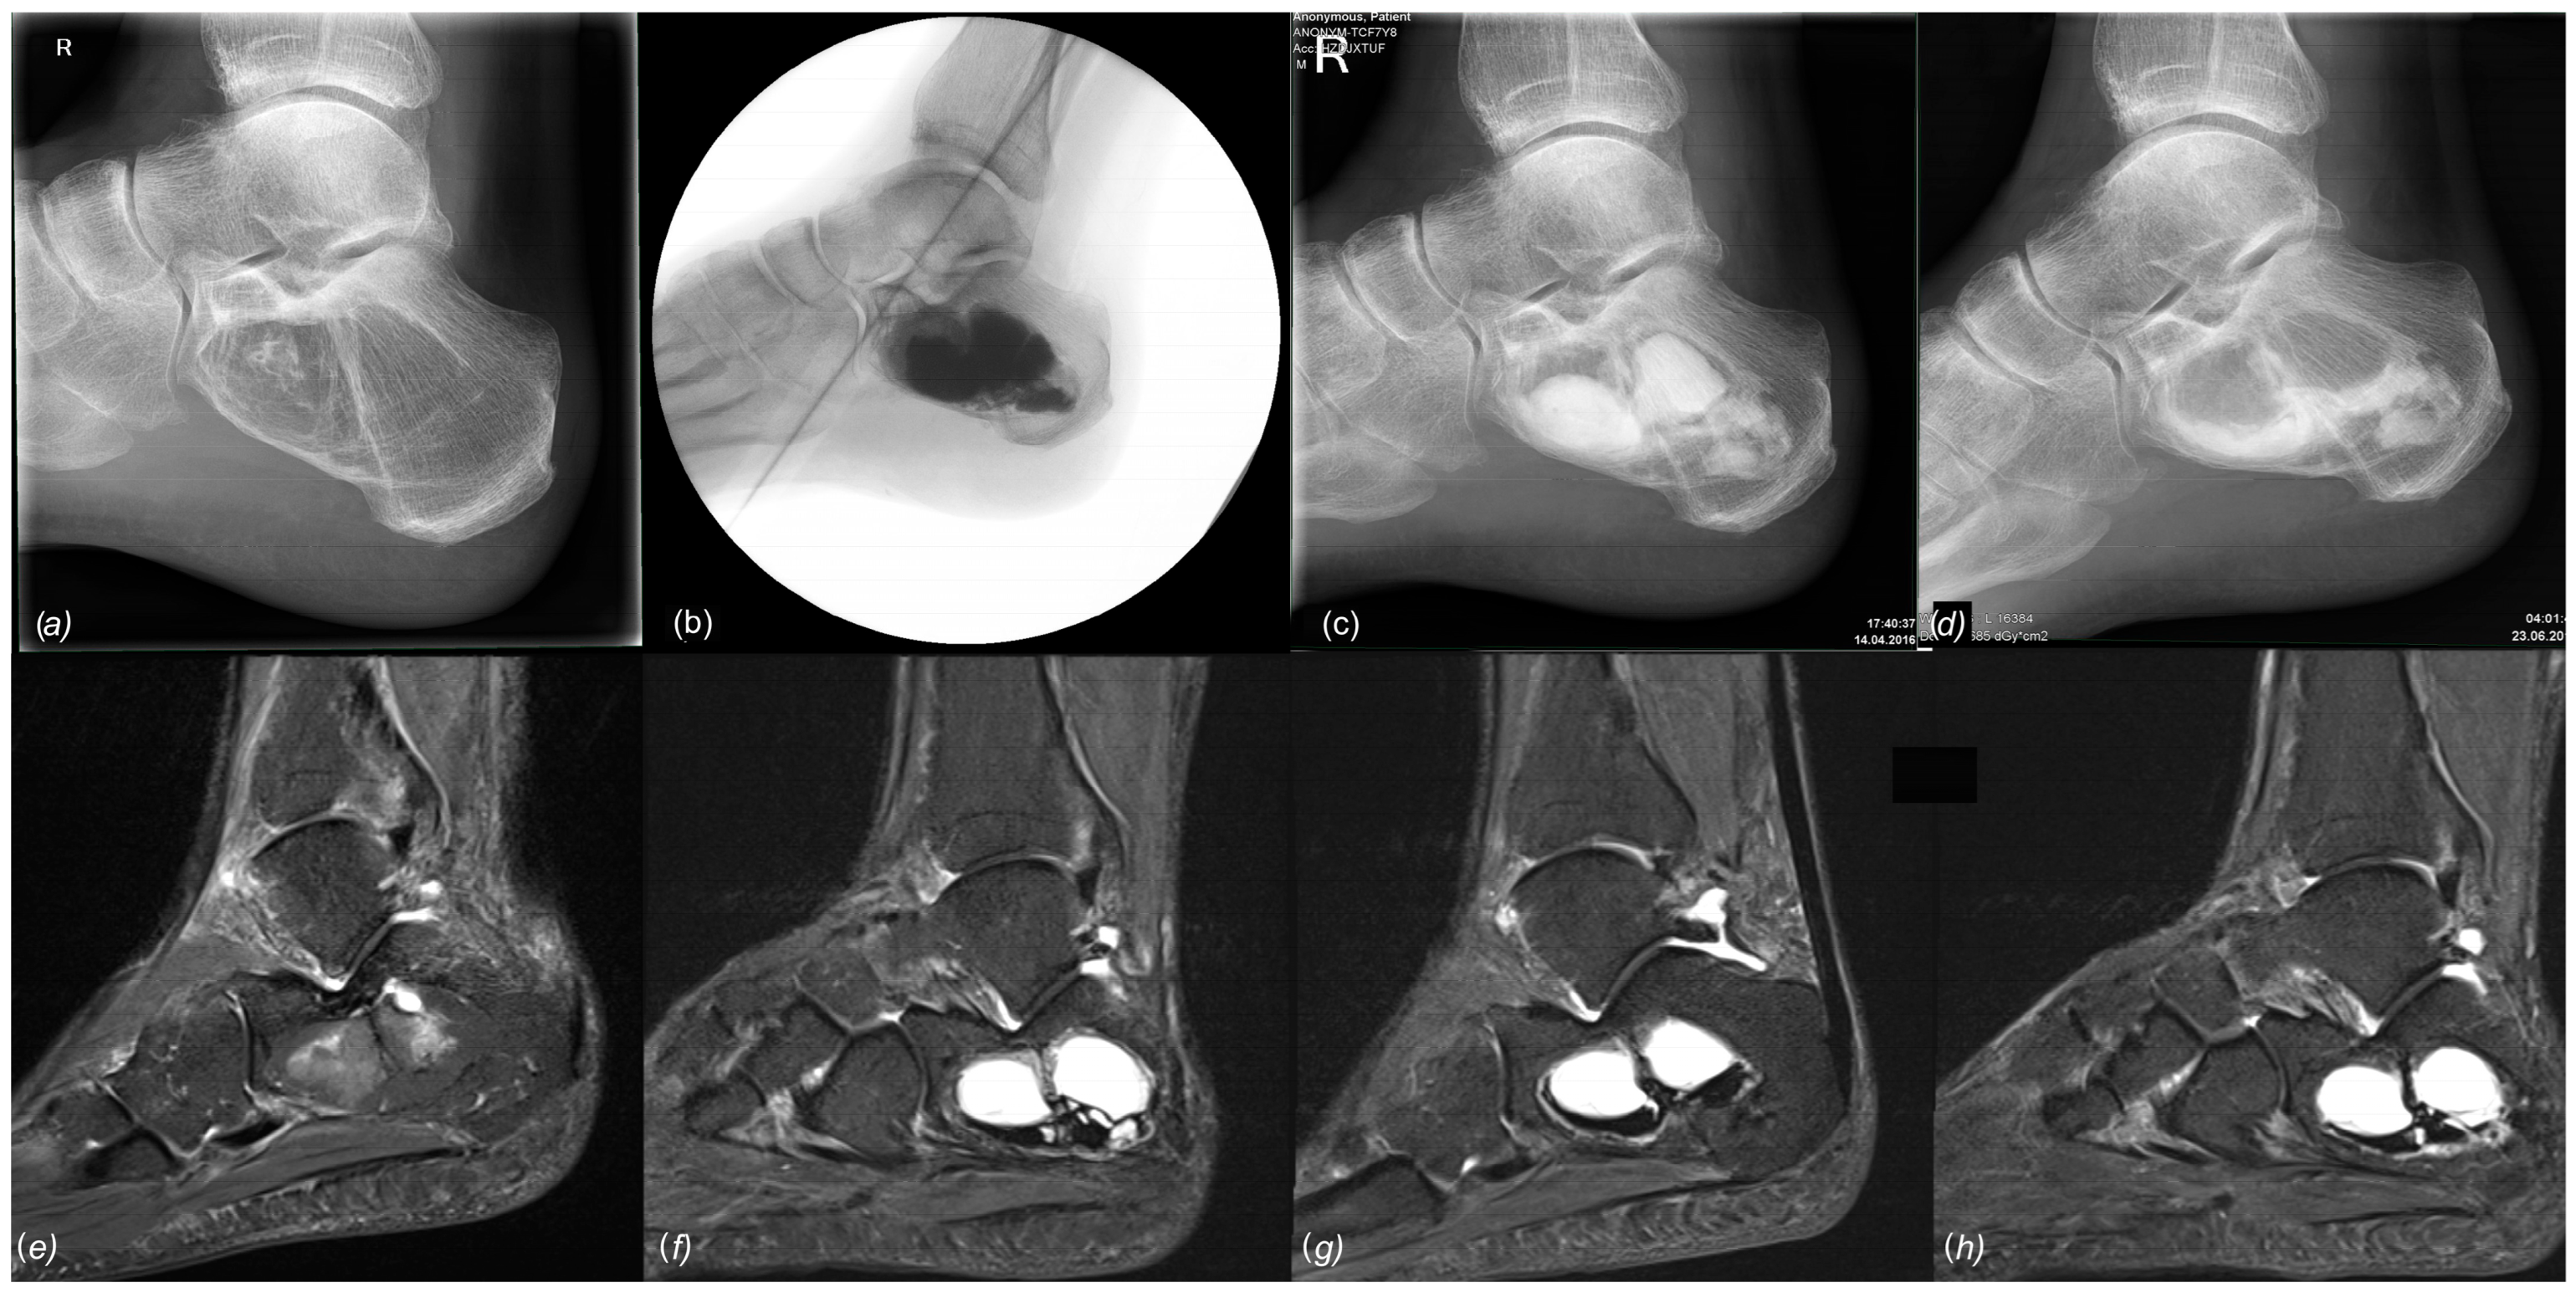

Figure 10.

Conventional radiological and MR tomographic follow-up of case 23: (a) preop, (b) 3 days postop, (c) 8 weeks postop, and (d) 3.5 months postop. Leakage of Cerament© was observed clinically (“white-out”) and radiologically.